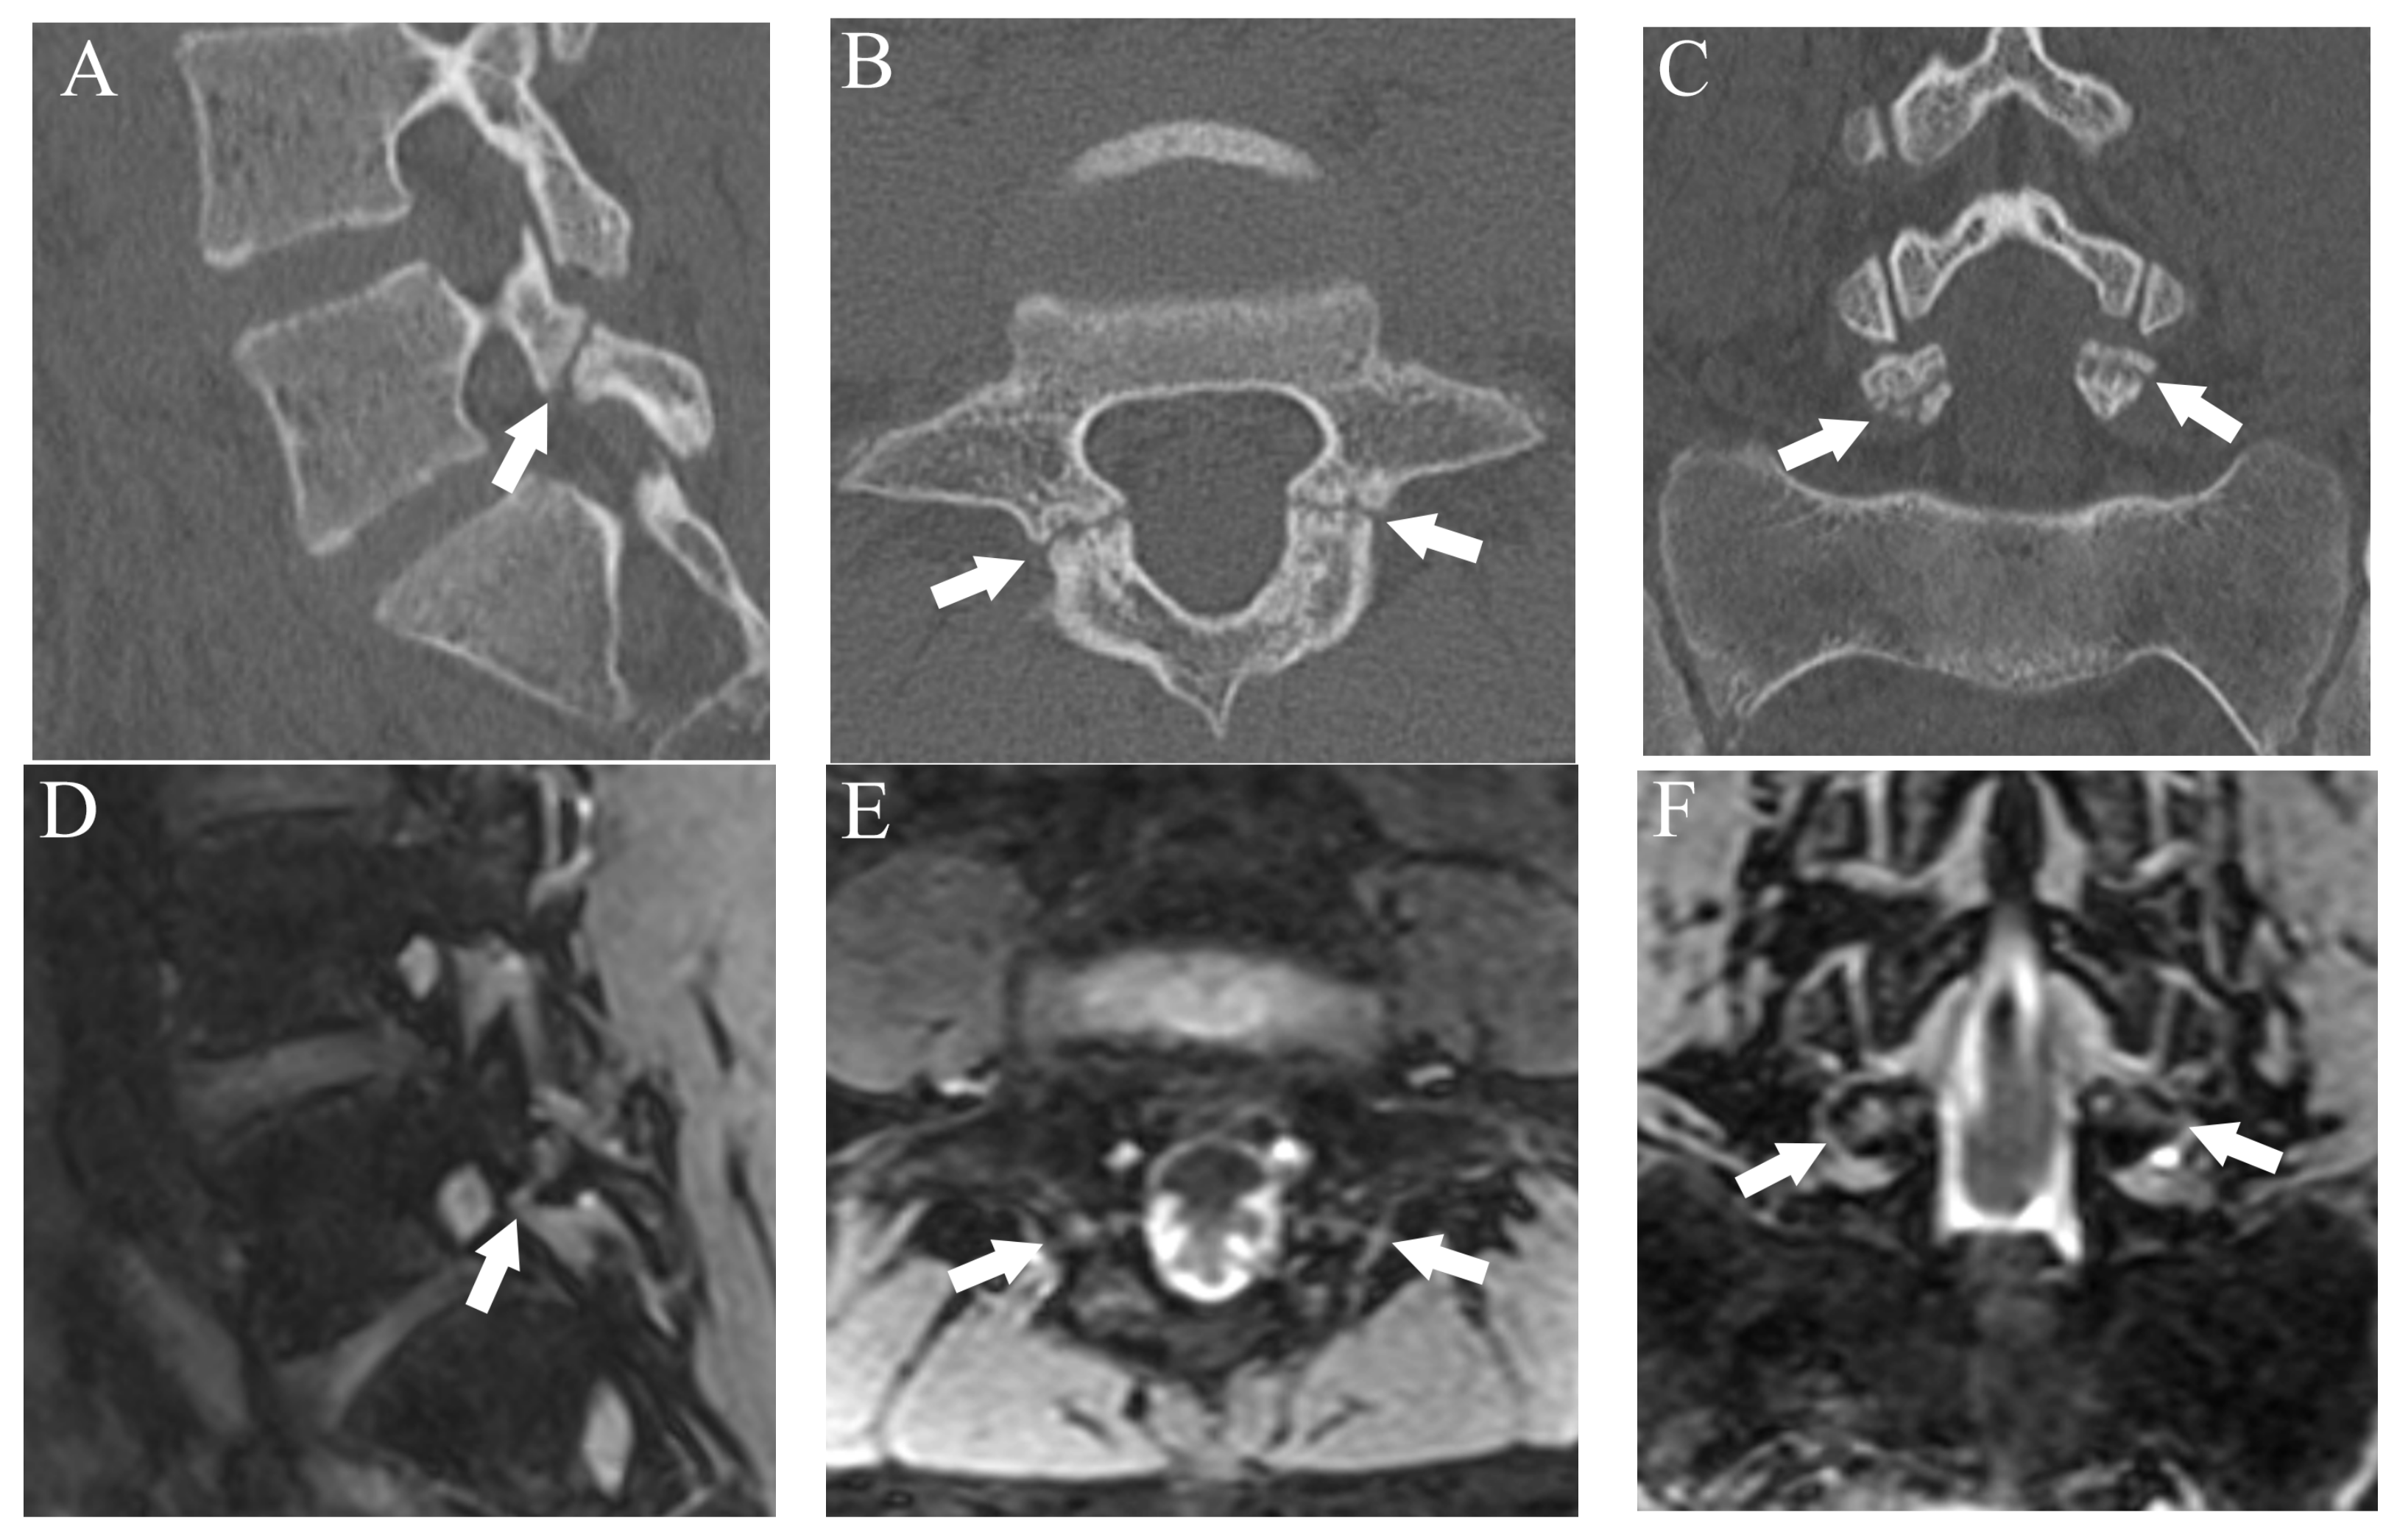

Figure 5.

Comparison of bilateral grade 3 fractures at L5 from an 11-year-old male in multiple planes between CT and DESS. (A–C) CT shows complete fractures in L5 pars interarticularis on the right-sided sagittal, axial, and coronal plane, respectively (arrows). (D–F) DESS shows comparable complete fracture on the right-sided sagittal, axial, and coronal plane, respectively (arrows).

Comparison of grade 2 fracture at the right pars interarticularis at L5 from a 14-year-old male in multiple planes between CT and DESS. (A–C) CT shows grade 2 fracture on the right pars interarticularis on the right-sided sagittal, axial, and coronal plane, respectively (arrows). On the axial plane, fracture of the left side is also delineated (thin arrow). (D–F) DESS shows grade 2 fractures comparable to CT on the right-sided sagittal, axial, and coronal plane, respectively (arrows). The sagittal and axial images delineate BME around the fracture (arrowhead), and the left pars interarticularis fracture is also delineated on the axial image (thin arrow).